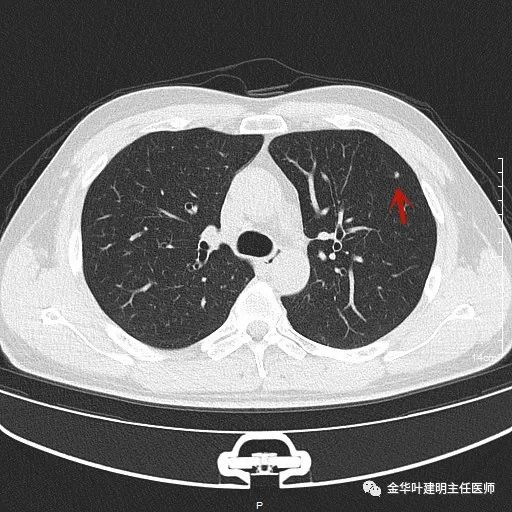

上图示隐球菌性结节。是典型的表现,高密度结节,周围部位,病灶有晕征,收缩力弱(邻近胸膜无牵拉凹陷)。